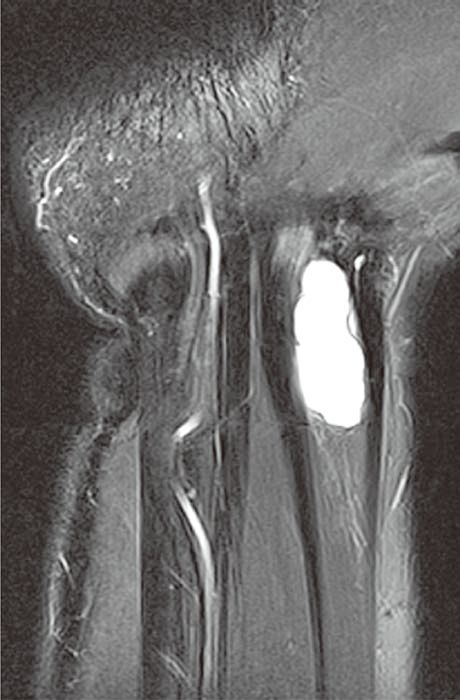

图2腕管腱鞘囊肿

A

B

C

横轴位(A)和冠状位(B)脂肪抑制T2WI示腕管内较大的腱鞘囊肿,内含液体而呈高信号。冠状位脂肪抑制增强T1WI(C)示囊壁强化而囊液不强化